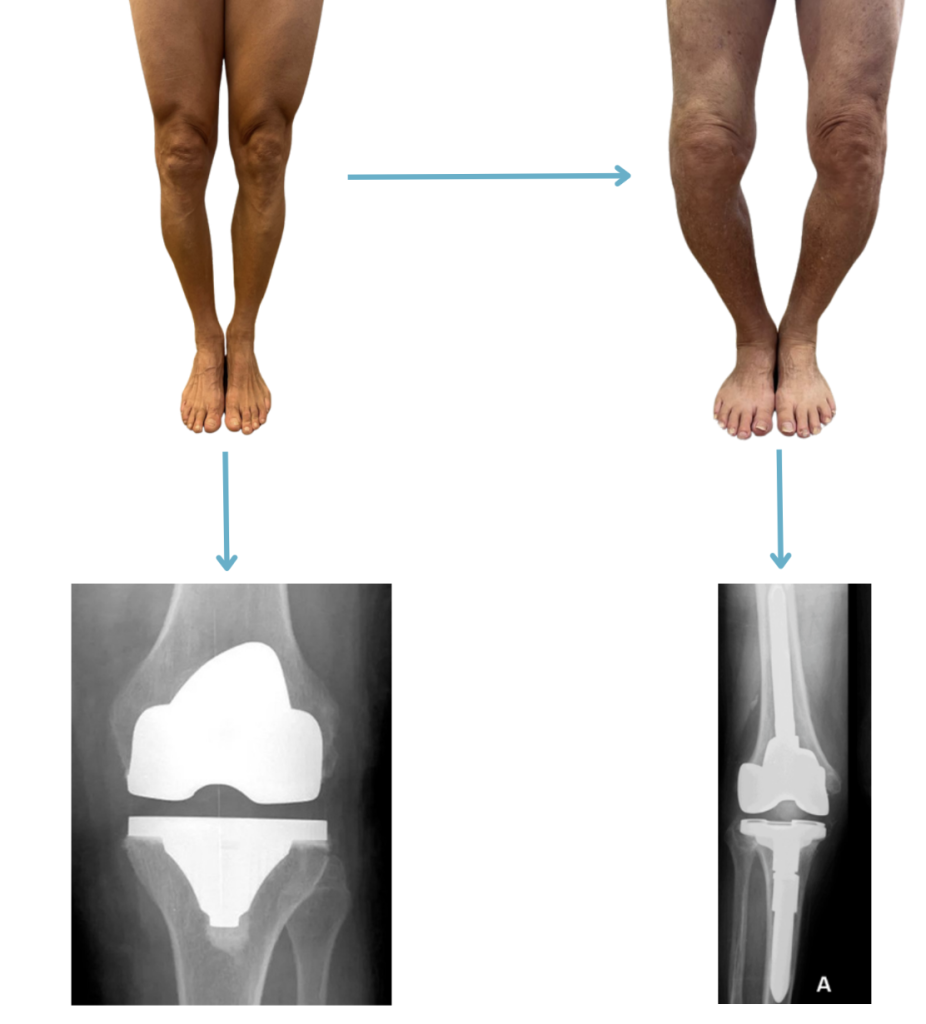

– Pernas que vão entortando cada vez mais. É comum encontrarmos alteração no alinhamento das pernas em pacientes que possuem artrose. Muitas vezes, conforme os anos passam e a gravidade da artrose aumenta, as pernas podem entortar progressivamente.

Sempre que fazemos uma prótese de joelho, o principal objetivo é realinhar as pernas, para que as mesmas fiquem retas. Quando a prótese é realizada e as pernas continuam tortas, mesmo após a cirurgia, muito provavelmente essa prótese não terá a duração máxima possível e teremos uma chance maior de que os implantes se desgastem ou se soltem. Quando a perna fica muito torta, a realização da

cirurgia e a correção do alinhamento dos membros inferiores acaba ficando muito mais desafiadora do que em casos onde as pernas ainda não estão muito tortas.

Em alguns casos, a perna fica tão desalinhada, que para desentortar, se faz necessário o uso de próteses especiais com uma haste metálica que vai por dentro do osso, para aumentar a estabilidade e conseguir endireitar os joelhos. Essa prótese especial (prótese de revisão) possui um número maior de complicações do que a prótese convencional (prótese primaria). Portanto se suas pernas estão entortando cada vez mais, pode ser que esteja na hora de realizar a cirurgia de artroplastia.

Quanto mais torta a perna for ficando, mais difícil será para corrigirmos o alinhamento dos membros inferiores. Em deformidades extremas, igual ao paciente da direita, se faz necessário utilizar uma prótese especial com uma haste metálica que vai por dentro do osso. Esse tipo de cirurgia é mais desafiadora e pode ter mais complicações. O paciente da esquerda também possui as pernas tortas, porém em uma intensidade muito menor. No caso dele, podemos utilizar a prótese tradicional primária, que possui menos complicações, sendo uma cirurgia tecnicamente menos desafiadora.